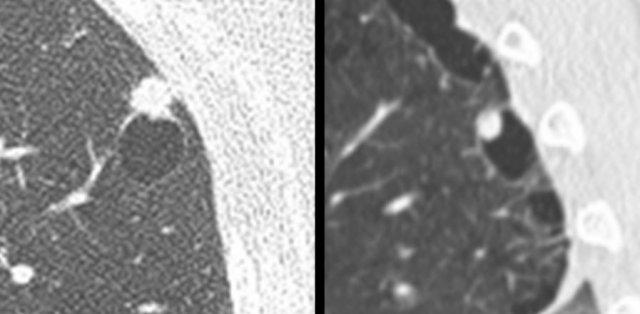

Ví dụ về ung thư phổi dạng nang với thành phần đặc hướng ngoại (bảng trái) và hướng nội (bảng phải).

Nốt phổi dạng nang có thể được định nghĩa là vùng đậm độ đặc và/hoặc kính mờ liên quan đến một khoang khí nhu mô có ranh giới rõ.

Nốt dạng nang có thể biểu hiện:

- Thành phần đặc hướng ngoại hoặc hướng nội tiếp giáp với khoang khí dạng nang (hình).